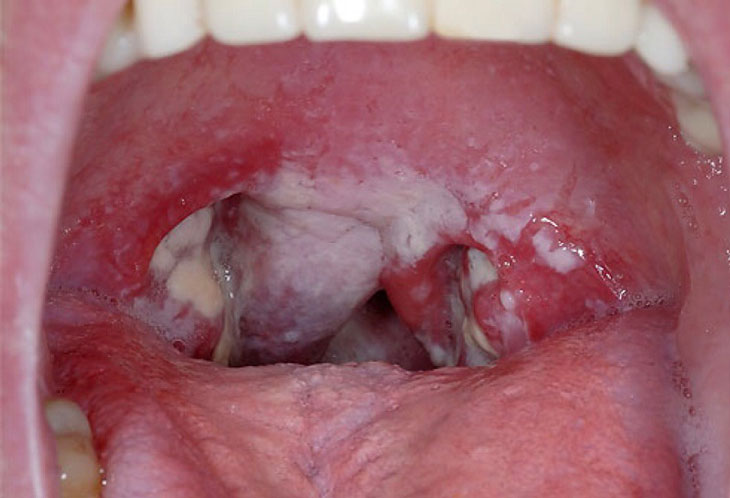

Giả mạc hai bên thành họng, có màu trắng ngà, xám, đen, dai, dính, dễ chảy máu.

Giả mạc hai bên thành họng, có màu trắng ngà, xám, đen, dai, dính, dễ chảy máu là triệu chứng của bệnh bạch hầu